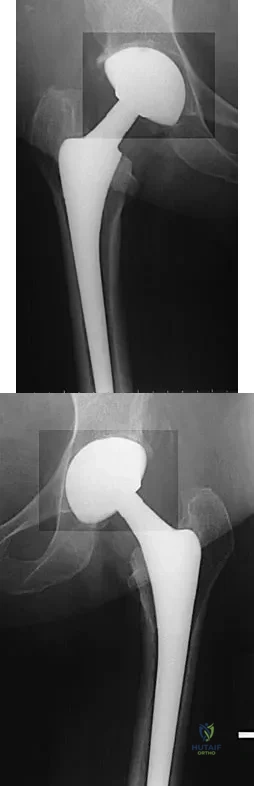

Question 325High Yield

A 68-year-old woman underwent a successful total right hip arthroplasty with a metal-on-metal articulation and cementless porous-coated components. Three months later, she underwent identical surgery on the left hip. Three months after surgery on the left hip, she reports groin pain on ambulation. Examination reveals significant groin discomfort with passive hip motion, particularly at the extremes of motion. Radiographs are shown in Figures 21a and 21b. Laboratory studies show an erythrocyte sedimentation rate of 35 mm/h and a C-reactive protein of 0.9. Aspiration yields scant growth of Staphylococcus epidermidis in the broth only, with no evidence of loosening on arthrography. A second aspiration yields scant growth of Staphylococcus epidermidis in the broth only. What is the most likely cause of the patient's pain?

Explanation

The difference in the clinical results combined with the laboratory findings points to infection. While there is a significant risk of false-positive findings with aspiration, the fact that two successive aspirations grew the same organism strongly suggests infection. The radiograph shows that there is more radiolucency around the left acetabular component than the right component. White RE: Evaluation of the painful total hip arthroplasty, in Callaghan JJ, Rosenberg AG, Rubash HE (eds): The Adult Hip. Philadelphia, PA, Lippincott-Raven, 1998, vol 2, pp 1377-1385.

References:

- Barrack RL, Harris WH: The value of aspiration of the hip joint before revision total hip arthroplasty. J Bone Joint Surg Am 1993;75:66-76.